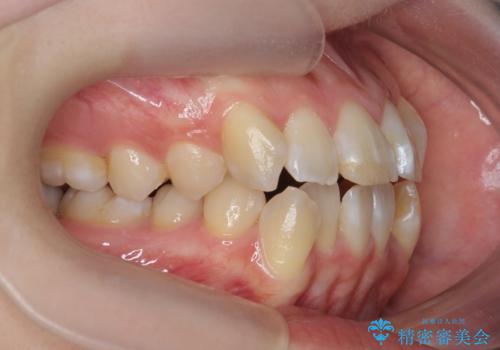

突き出た前歯を治したい 小臼歯抜歯+マルチブラケット矯正

- 突き出て、気になる前歯の角度の改善を求めて来院されました。

前歯の角度を改善するために小臼歯4本の抜歯を行いワイヤー マルチブラケットを用いて、しっかりと前歯の角度を改善する治療計画としました。